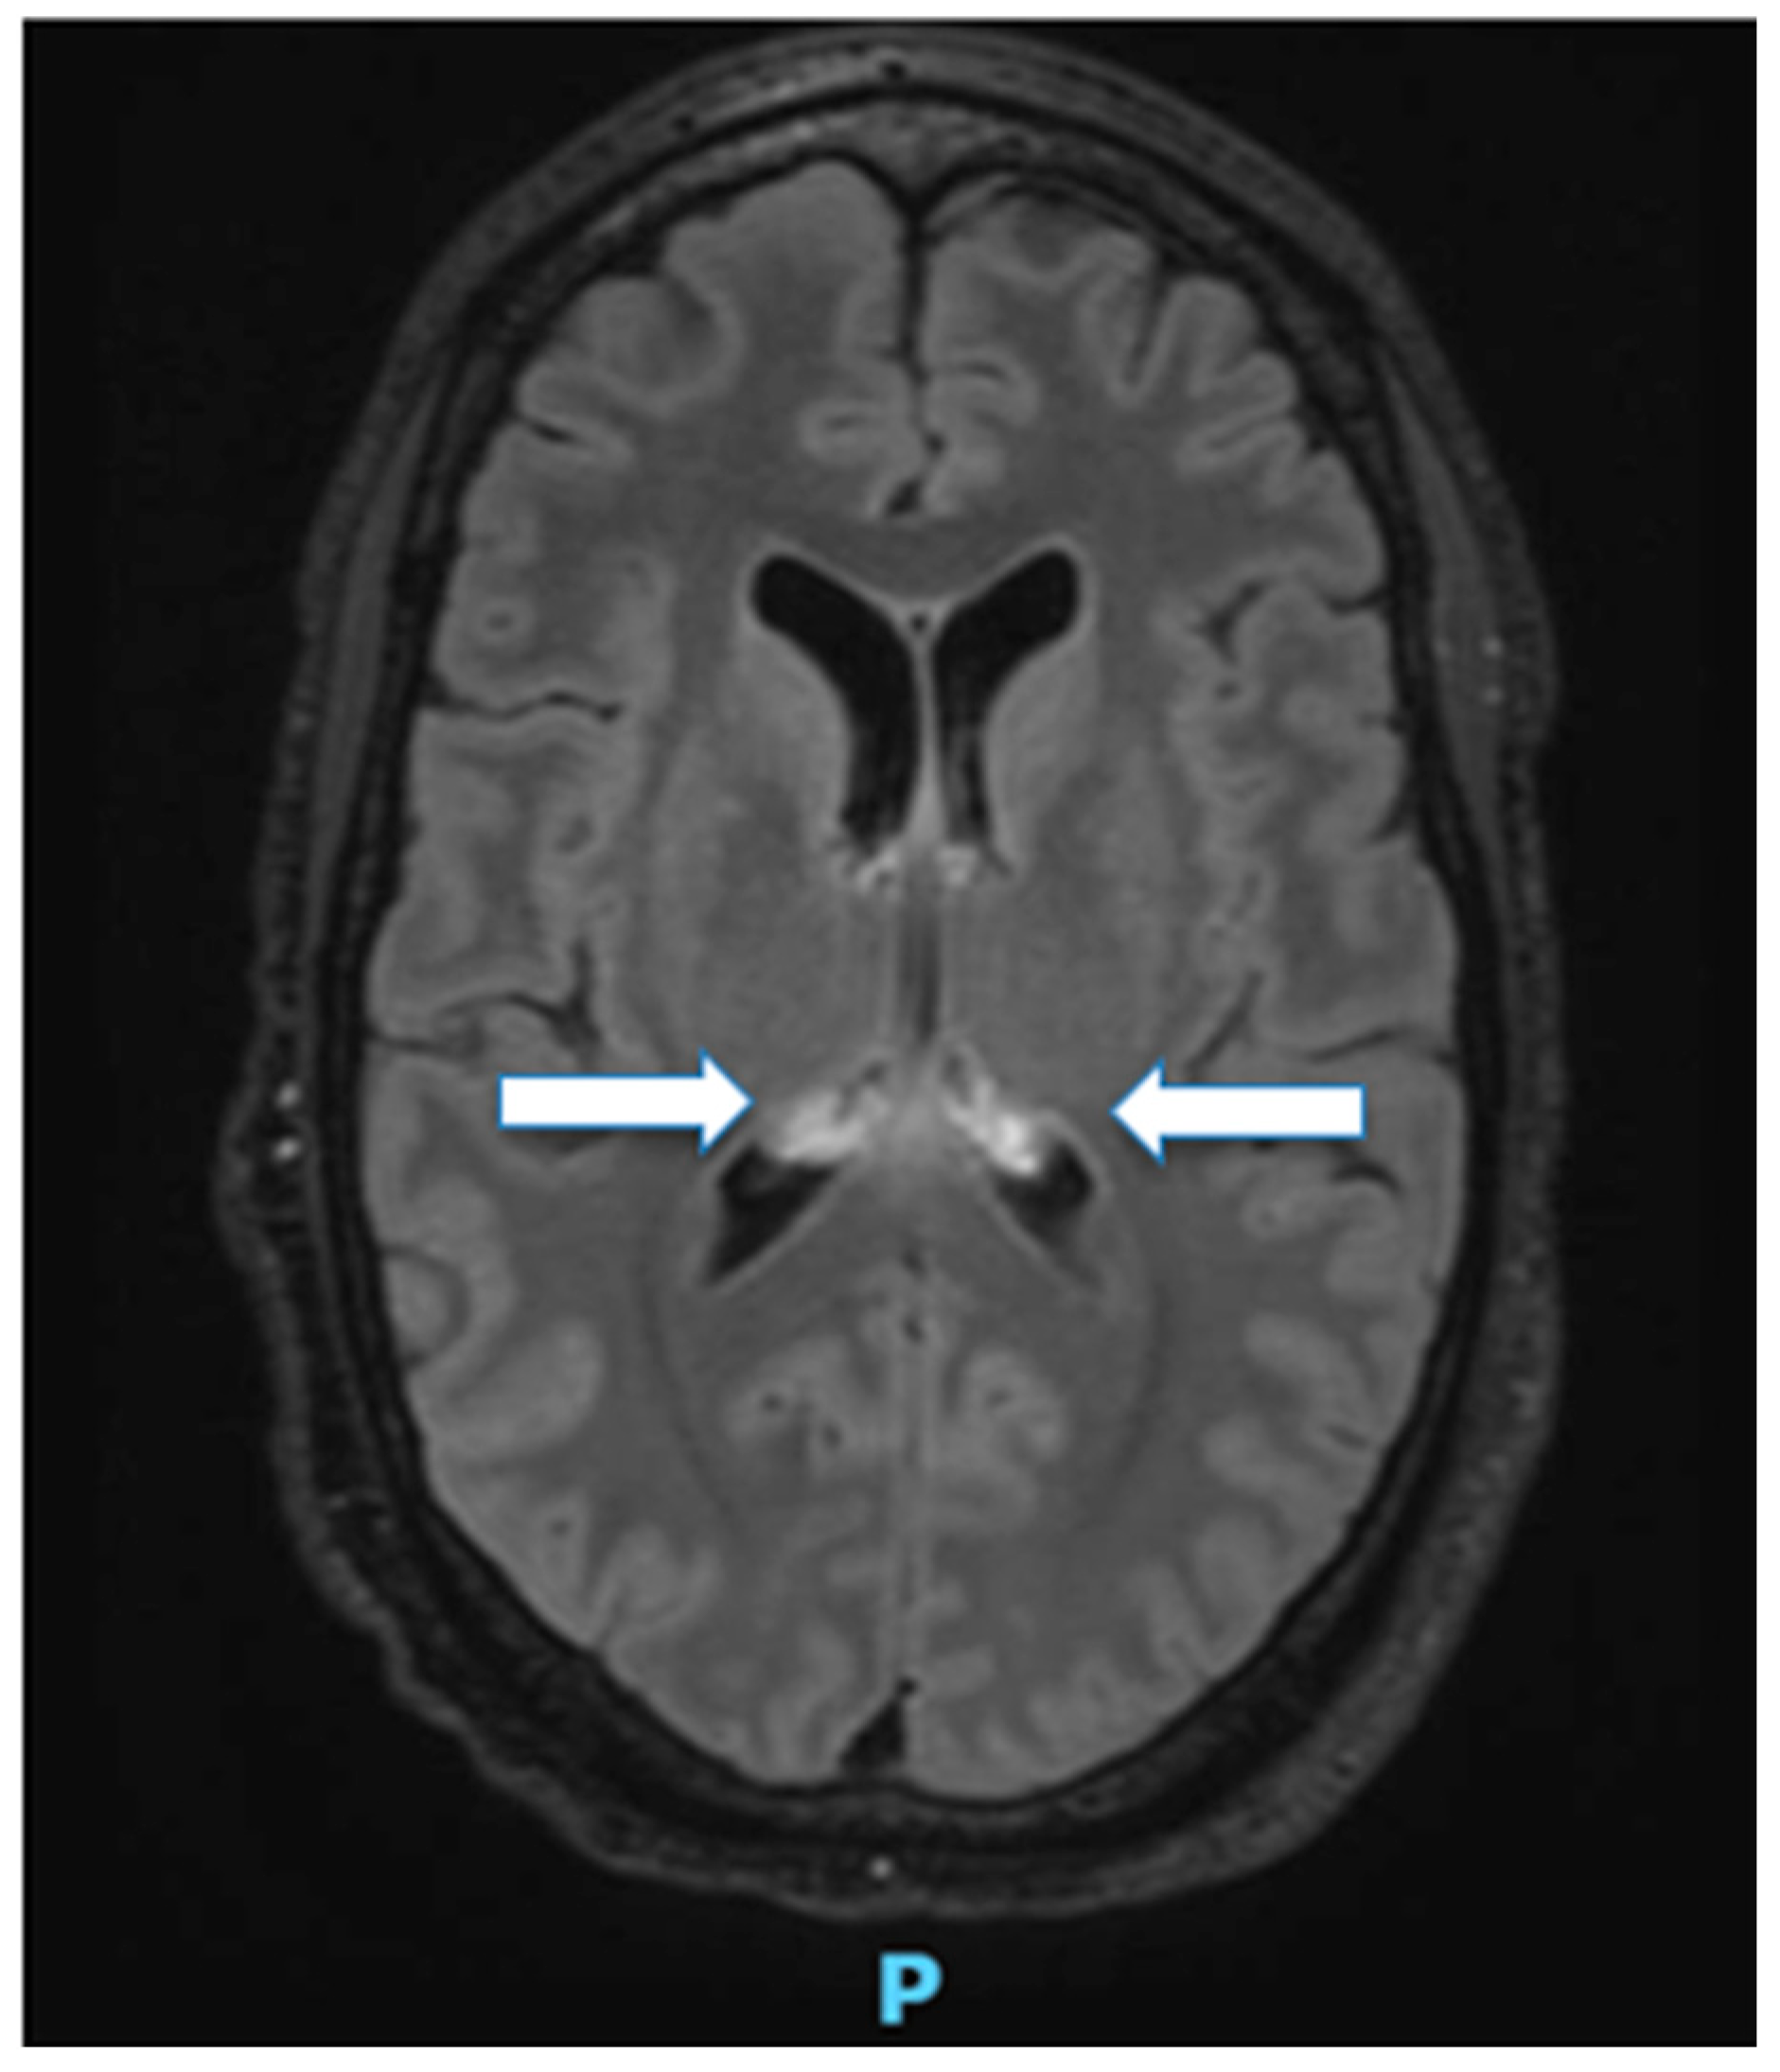

- Moors, S.; Nakhostin, D.; Ilchenko, D.; Kulcsar, Z.; Starkey, J.; Winklhofer, S.; Ineichen, B.V. Cytotoxic lesions of the corpus callosum: A systematic review. Eur. Radiol. 2024, 34, 4628–4637. [Google Scholar] [CrossRef] [PubMed]

- Forestier, G.; de Beaurepaire, I.; Bornet, G.; Boulois, G. Cytotoxic lesion of the corpus callosum as presenting neuroradiological manifestation of COVID-2019 infection. J. Neurol. 2021, 268, 1595–1597. [Google Scholar] [CrossRef]

- Kopyta, I.; Siemek-Mitela, J.; Damps, M.; Machnikowska-Sokolowska, M.; Gruszczynska, K. Cytotoxic Lesions of the Corpus Callosum (CLOCCs) in a Patient with Epstein-Barr Infection: A Case Report and Literature Review. Brain Sci. 2025, 15, 260. [Google Scholar] [CrossRef]

- Park, H.J.; Song, S.H.; Suh, S.H.; Choi, H.S.; Bae, E.H.; Ma, S.K.; Kim, S.W.; Kim, C.S. Cytotoxic Lesions of the Corpus Callosum Preceding Osmotic Demyelination Syndrome in Hypernatremia and Hyperosmolar Hyperglycemic State: A Case Report. Electrolyte Blood Press. 2025, 23, 11–16. [Google Scholar] [CrossRef]